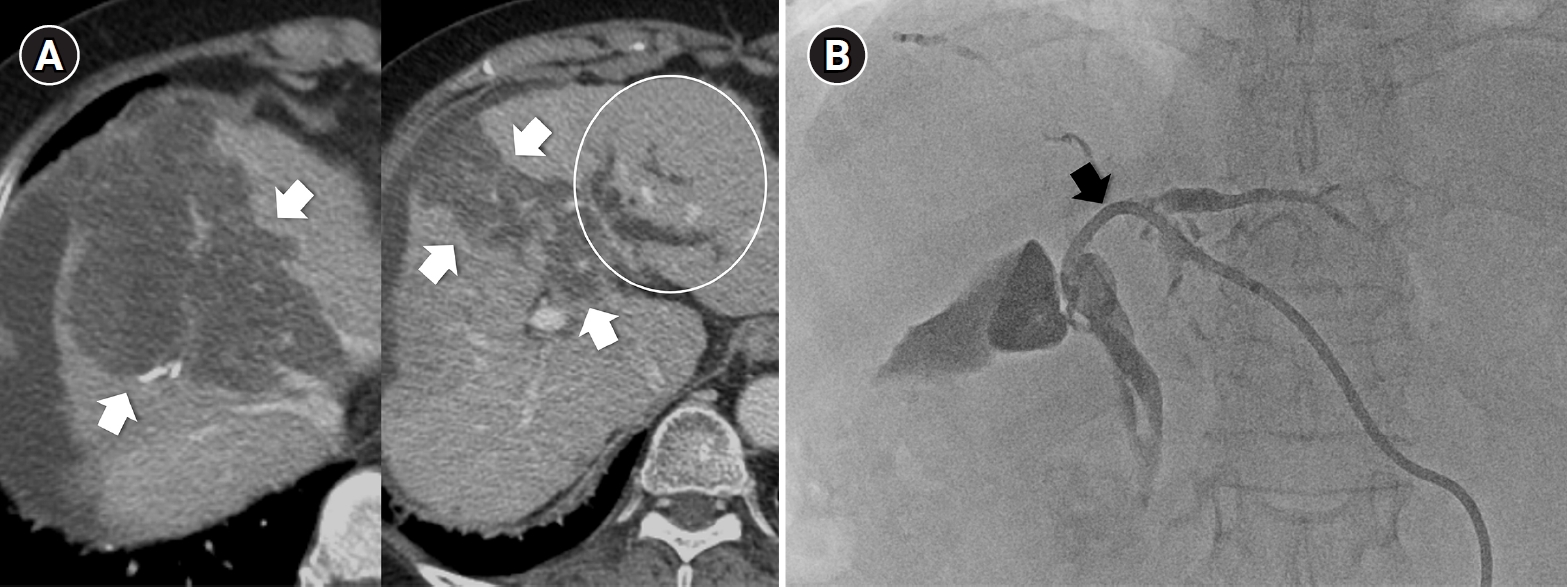

Sequential transarterial radioembolization (TARE) followed by transarterial chemoembolization (TACE) in a 77-year-old man with large hepatocellular carcinoma. (A) Magnetic resonance imaging and angiography show a 12.5-cm conglomerated mass (arrows) with multiple satellite nodules in segments 5, 6, and 7. (B) Sequential TARE was planned because a single session could not achieve sufficient tumor dose owing to lung dose limitation. In TARE #1 (5.0 GBq resin microspheres), perfused liver dose was 178 Gy and lung dose was 9.6 Gy. In TARE #2 (5.5 GBq resin microspheres), perfused liver dose was 255 Gy and lung dose was 12.2 Gy. Post-treatment Y-90 positron emission tomography/computed tomography demonstrates heterogeneous intratumoral Y-90 activity in the tumors. (C) Angiography 5 months after TARE #2 shows decreased tumor staining (arrows) in the right lobe. TACE was performed through multiple subsegmental branches supplying residual tumor. (D) After two additional TACE sessions (not shown), the computed tomography obtained 2 years after the initial TARE showed decreased tumor size, near-complete disappearance of arterial enhancement, and partial lipiodol uptake (arrows) in the tumor.

TARE and TACE should not be regarded as competing procedures but as complementary components of a personalized treatment strategy for HCC. TARE offers durable local control and better tolerability, making it suitable for localized or large tumors in patients with preserved hepatic function or limited procedural tolerance. In contrast, TACE provides procedural precision, broad applicability, and repeatability, maintaining its role as the backbone of transarterial therapy across most clinical stages. In clinical practice, sequential or combined use may achieve a better balance between efficacy and safety (Figs. 5, 6) [34]. Ultimately, the choice between TARE and TACE should be individualized according to tumor characteristics, hepatic reserve, and institutional expertise, and that optimal HCC management depends on integration rather than substitution.